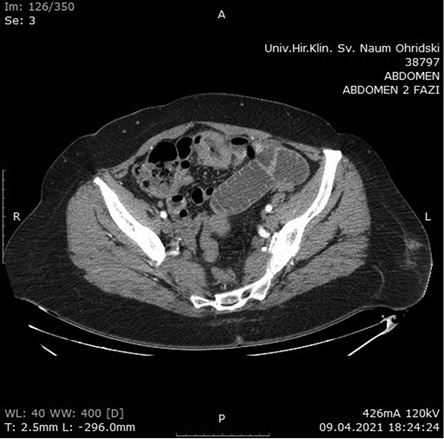

Contrast-enhanced Computerized Tomography (CECT) of the abdomen was the next diagnostics tool. The small intestine was presented with dilated loops, formed “air fluid levels” and free fluid in the Douglas pouch. The tumor formation itself was not detected by the radiologist on this scan (Figure 2).

Figure 2. CECT of abdomen with signs of small bowel obstruction